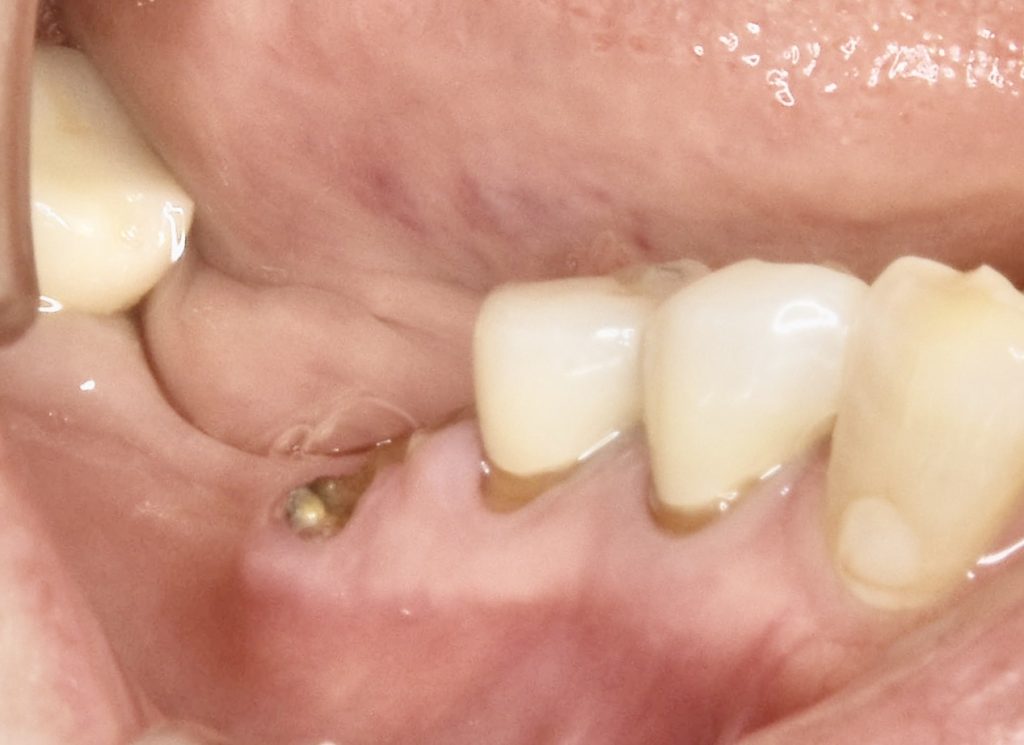

下記の症例はインプラントだけ埋入すれば良いわけではありません。

周囲環境を整え長期的に安定し、長持ちさせるインプラントを目指す必要があります。

その為に歯肉を移植しインプラント周囲に強い抵抗力を持つ歯肉を作る事が大切です。